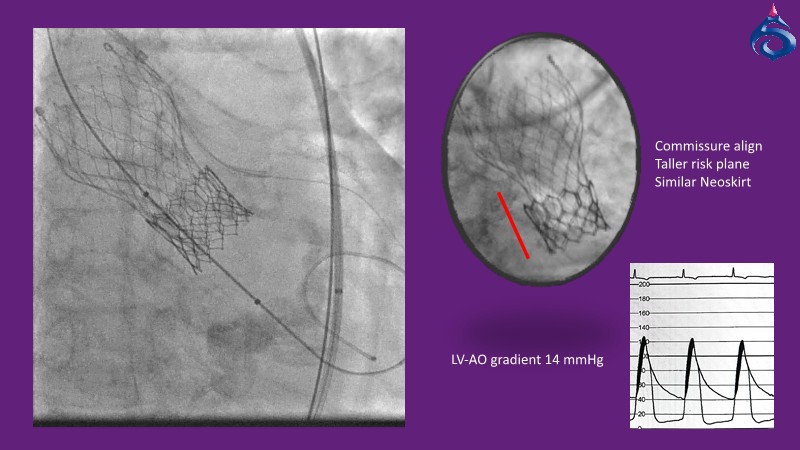

Watch this expert-led session on the latest Evolut TAVI advancements, device selection for small annulus cases, and strategies for complex anatomies. Learn about redo-TAVI feasibility and key 1-year data from the SMART trial.

• To master implantation techniques and discern the latest technological evolutions for treating patients with complex anatomies